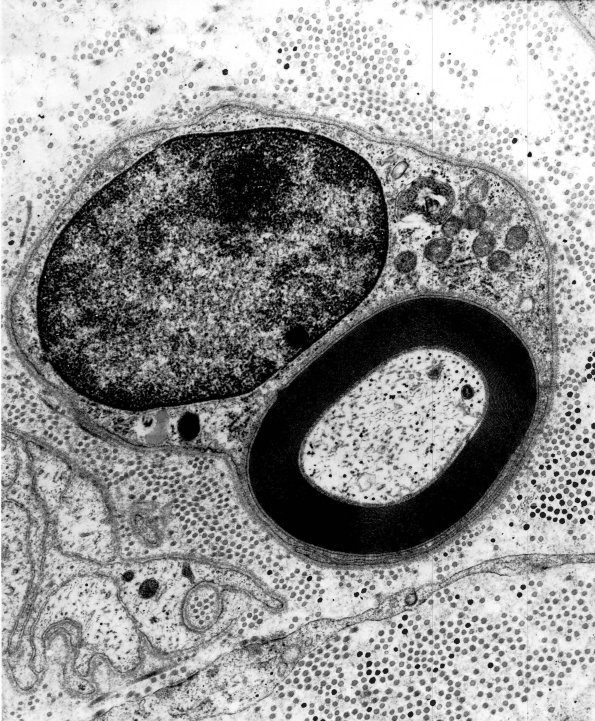

8A1,2 A normal myelinated axon at multiple magnifications. (electron micrographs)